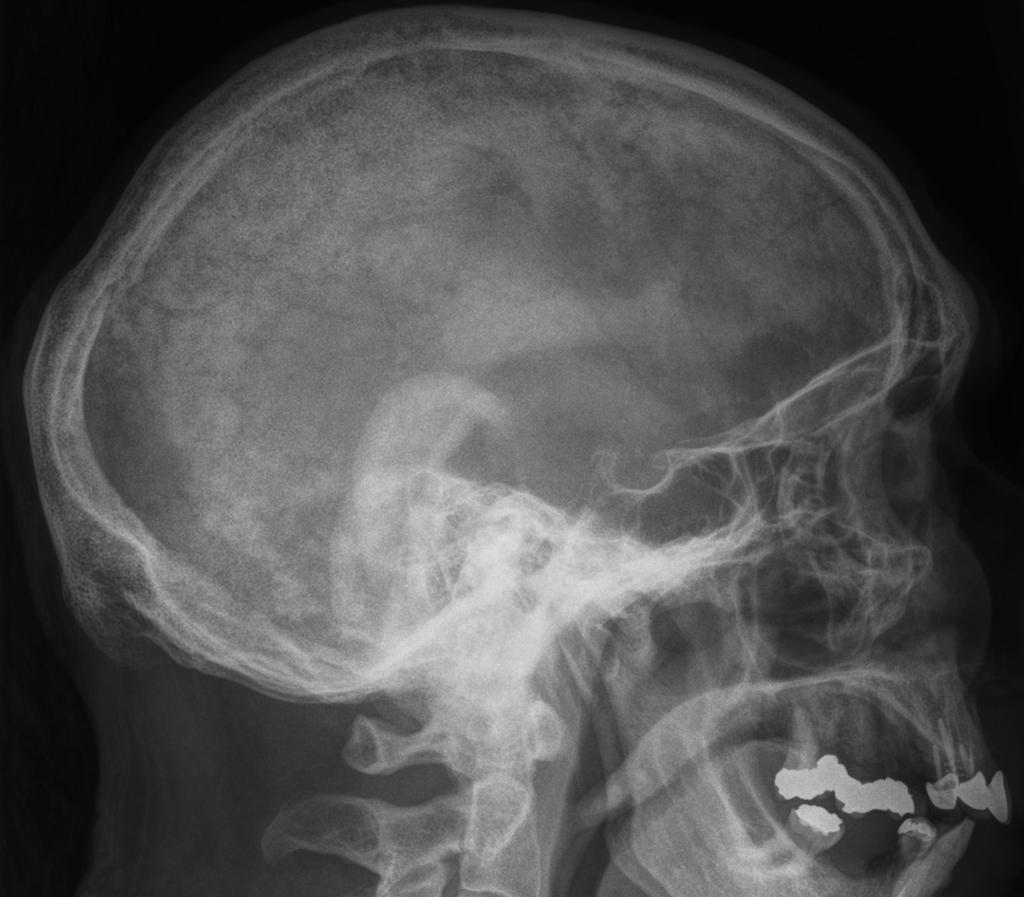

Paget Disease of Bone RadioGraphics Paget's Disease Of Bone Labs paget disease of bone is a benign skeletal disorder characterized by focal areas of increased bone resorption and disorganized bone formation. paget disease is a skeletal growth disorder in which abnormalities such as unusual bone growth can occur in several multifactorial ways. This is the best test for diagnosing paget's disease. A simple blood test can be carried.. Paget's Disease Of Bone Labs.